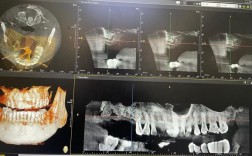

判断建议:前牙美学修复、金属过敏倾向选锆;后牙修复、预算有限或骨条件复杂选钛,具体需经口腔CT检查后由医生评估。